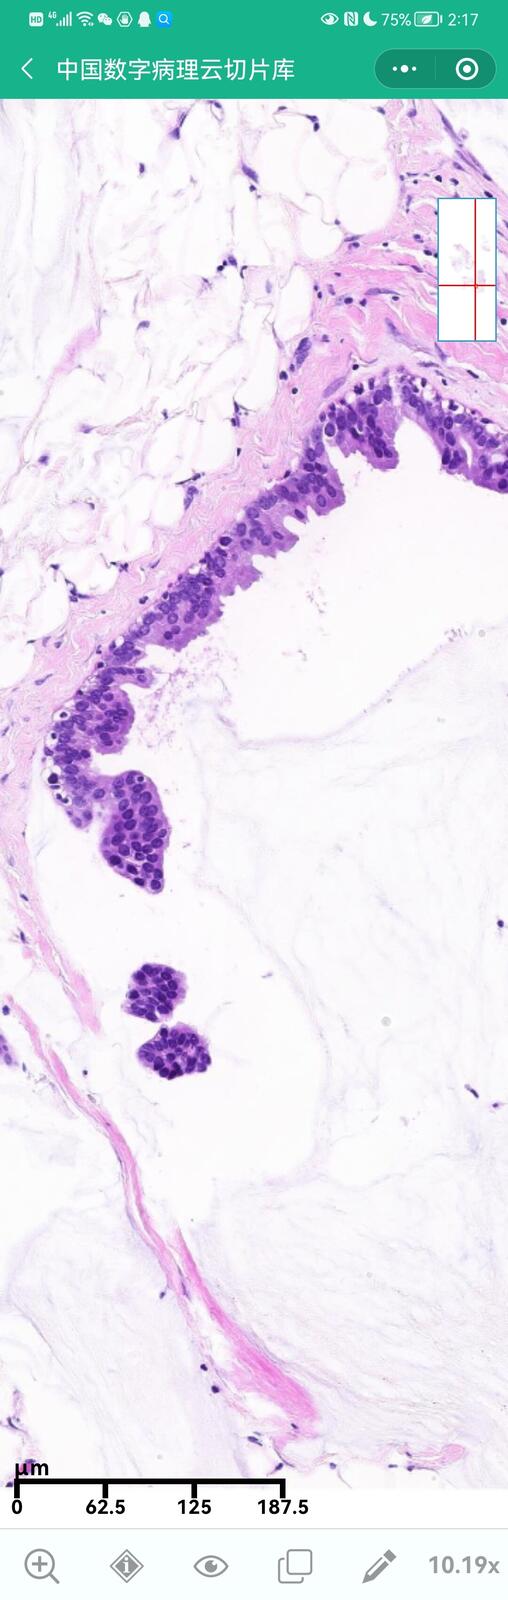

乳腺黏液性囊腺瘤伴导管内癌